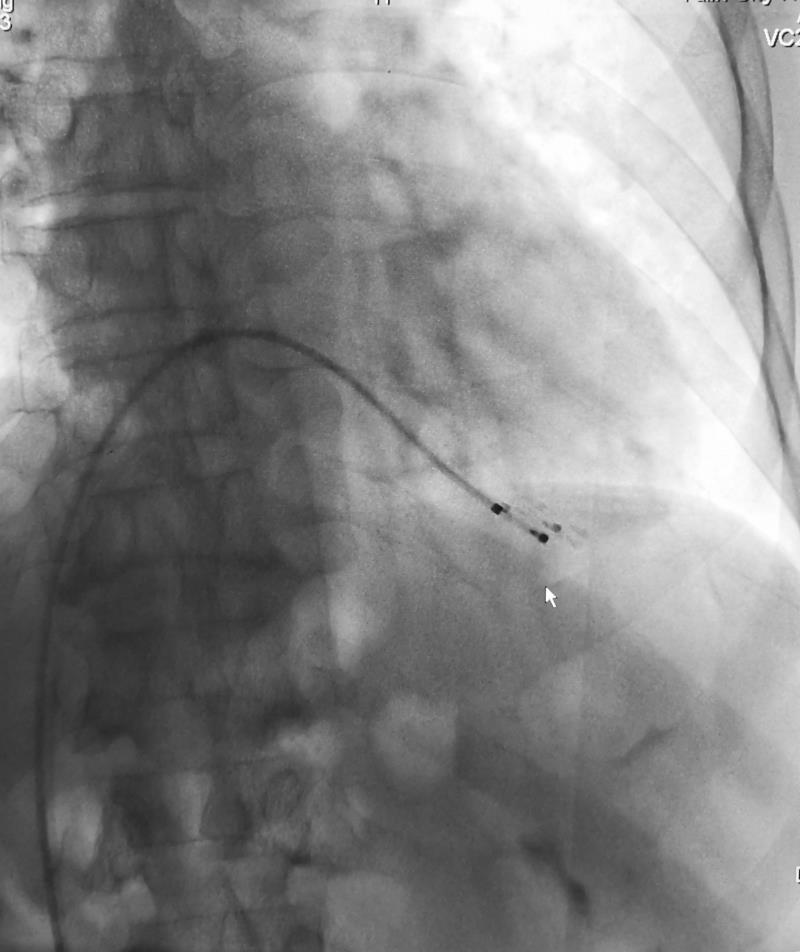

术中放置起搏器

术中,榆林二院心血管介入团队给患者放置心脏临时起搏器,为心脏保驾护航;麻醉科给予患者妥善全麻后,由榆林二院脑科医院神经内科一病区联合神经外科一病区,经过娴熟、精准的操作,顺利完成手术,术中术后未发生任何并发症。